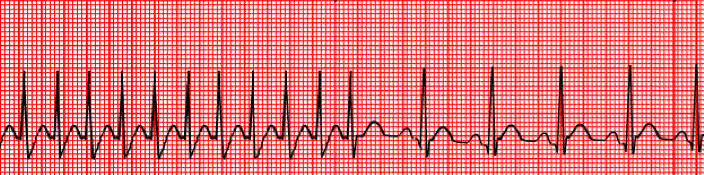

What is this rhythm?

What is one priority intervention?

Sinus Bradycardia

IV 0.5 - 1 mg Atropine